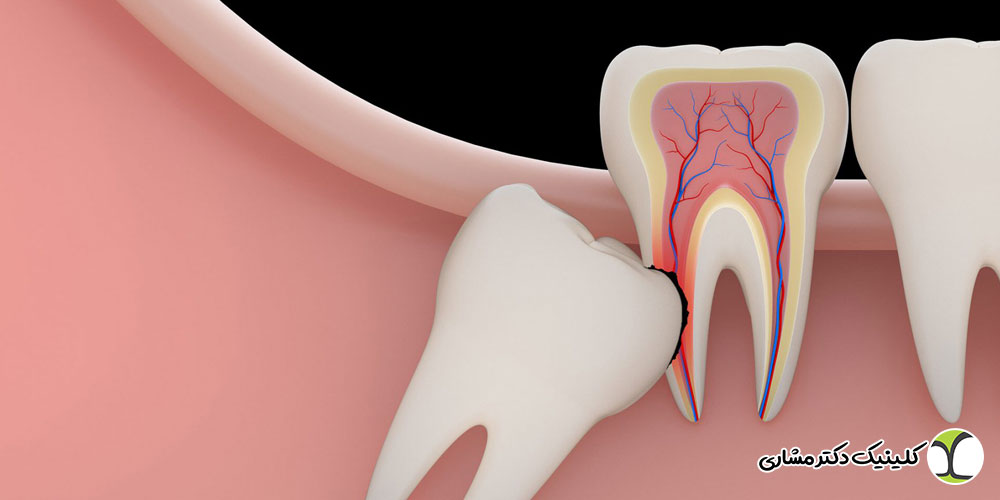

جراحی دندان عقل نهفته روی عصب چگونه انجام میشود؟

پس از بررسی تصاویر، جراح فک و صورت با توجه به میزان درگیری عصب، نوع جراحی را برنامهریزی میکند. مراحل کلی شامل:

- بیحسی موضعی (یا بیهوشی در موارد خاص)

- ایجاد دسترسی به استخوان فک

- برداشت کنترلشده استخوان اطراف دندان

- جدا کردن تاج یا ریشهها بهصورت مرحلهای

- خارج کردن دندان با کمترین فشار به عصب

- بخیه و کنترل ناحیه جراحی

در برخی موارد خاص، ممکن است از تکنیکهایی مانند کرونکتومی (برداشت تاج دندان و باقی گذاشتن ریشه) برای کاهش خطر آسیب عصبی استفاده شود.